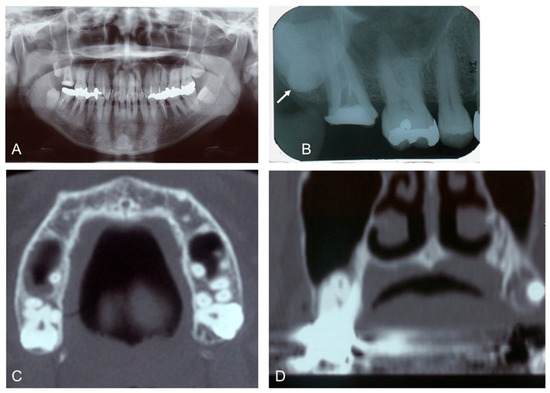

A 46-year-old female revealed a fistula at the apex of the palatal root of the upper right second molar (Tooth #2). She had a history of non-tuberculous mycobacteriosis, Hashimoto’s thyroiditis, and submucosal tumor of the large intestine. Clinical examination required the extraction of the upper right third molar (Tooth #1) and the palatal root of Tooth #1. Radiographic examination showed that the wisdom tooth (Tooth #1) was horizontally impacted in the maxilla and had the apex of a single root placed between the buccal and palatal roots of Tooth #2 (Figure 1).

Figure 1. Initial X-ray images of the 46-year-old female patient. (A): Panoramic image. Note: impacted wisdom teeth (#1, 16, 17, 32). (B): Dental image (#1, 2, 3, 4). Arrow indicates horizontally impacted tooth (#1). (C): CT (axial image). (D): CT (coronal image) showing root apex of upper right third molar (#1) placed between buccal and palatal roots of upper right second molar (#2).